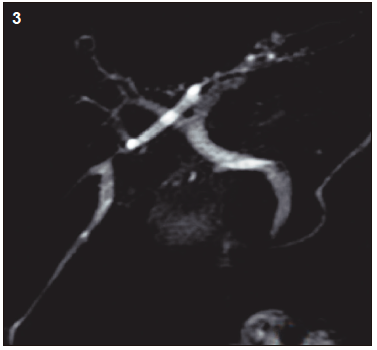

Figura 1. Colangioresonancia magnética

Figura 3. Colangioresonancia al mes postoperatorio. Ausencia de litiasis residual

El estudio por colangioresonancia evidenció una variante anatómica biliar tipo 3 de la clasificación de Huang, ya que el conducto hepático posterior derecho drenaba en el conducto hepático izquierdo.1 Se observaron imágenes compatibles con litiasis intrahepática derecha y litiasis en el colédoco distal. La CPRE confirmó la presencia de la variante anatómica del patrón ductal hepático derecho y permitió realizar una canulación selectiva con posterior extracción de litos mediante balón y canastilla.2 El paciente tuvo una buena evolución clínica sin complicaciones.

La clasificación de Huang describe cinco variantes anatómicas del drenaje biliar. En la variante anatómica tipo 3, el conducto hepático posterior derecho drena en el hepático izquierdo. Esta variante, aunque poco frecuente, ha sido informada en 4 a 8% de los estudios por colangioresonancia.1 Su reconocimiento es fundamental debido a que se asocia con un riesgo mayor de lesión quirúrgica y puede dificultar el tratamiento endoscópico.4, 5